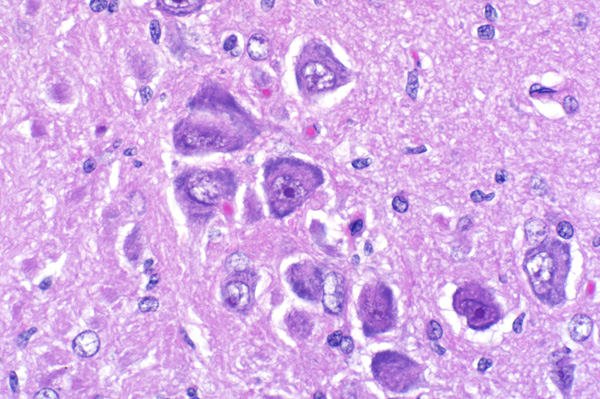

| 40x   |   Hematoxylin and Eosin | ||||

Some neurons have peripheralized Nissl substance and a "ground glass" appearance to the cytoplasm (chromatolysis) (arrows).